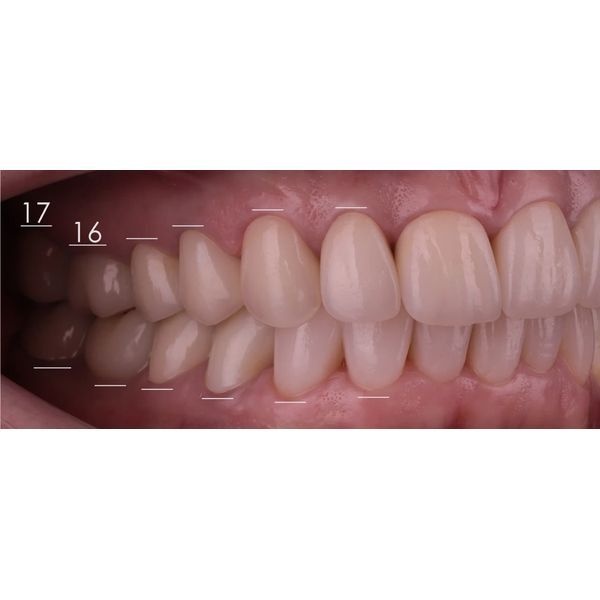

При осмотре выяснилось, что конструкции на центральных зубах хоть и выглядели эстетично, на них появились трещины и сколы, было нарушено краевое прилегание. Кроме того, у женщины наблюдалась стираемость зубов, особенно заметно стёрся нижний клык (зуб 3.3). На других зубах также присутствовали сколы.

Жевательные поверхности боковых зубов оставались гладкими. Это говорило о том, что у пациентки не было окклюзионных помех, которые могли бы спровоцировать проблемы с височно-нижнечелюстным суставом (ВНЧС), однако из-за отсутствия рельефа контакт между зубами-антагонистами плоскостной, а не точечный, поэтому мышцам приходилось прилагать больше усилий, чтобы пережевать пищу.

В этом случае нам удалось добиться оптимального окклюзионного контакта. На динамических и статических пробах видно плотное, равномерное смыкание всех зубов. Это не только эстетически выигрышно, но и функционально: теперь жевание стало эффективнее, а нагрузка на суставы — физиологичнее.